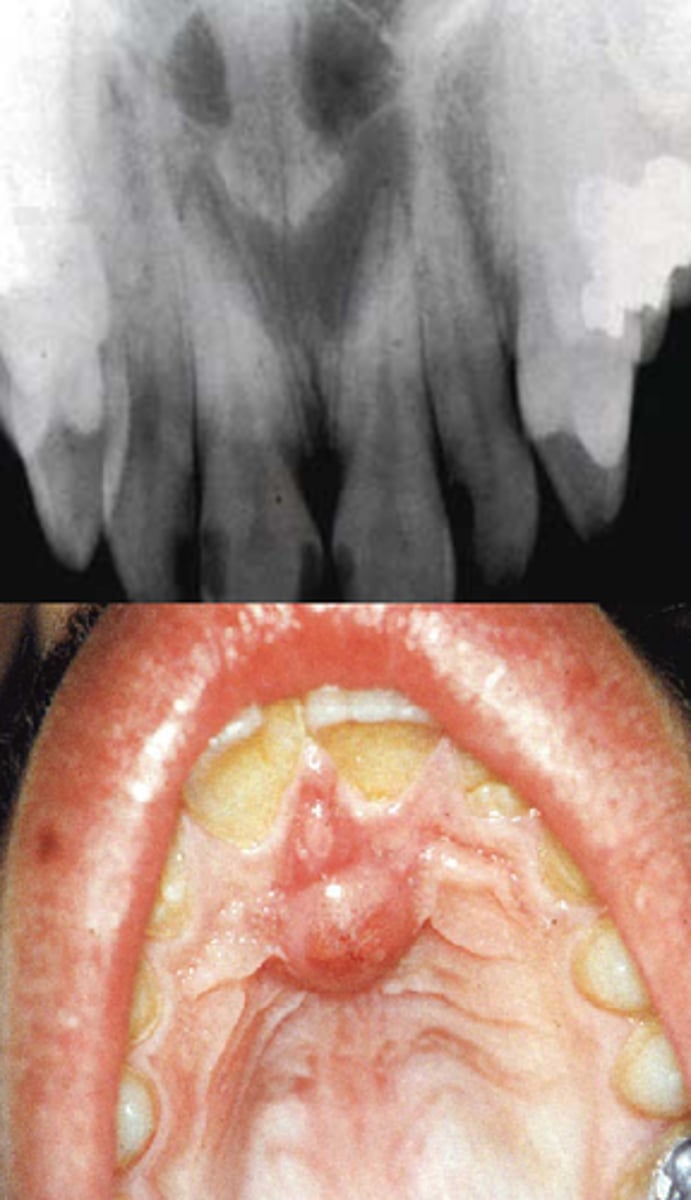

What are clinical features of nasopalatine duct cysts?

• pink swelling of incisive papilla area

• teeth are VITAL

• asymptomatic

What are radiographic features of nasopalatine duct cysts?

well-defined radiolucency btwn maxillary central incisors

• "heart-shaped" **KNOW FOR EXAM

What is a median palatal cyst?

more posterior form of nasopalatine canal cyst

• not heart-shaped

What are radiographic features of median palatal cysts?

well-defined unilocular radiolucency at midline hard palate